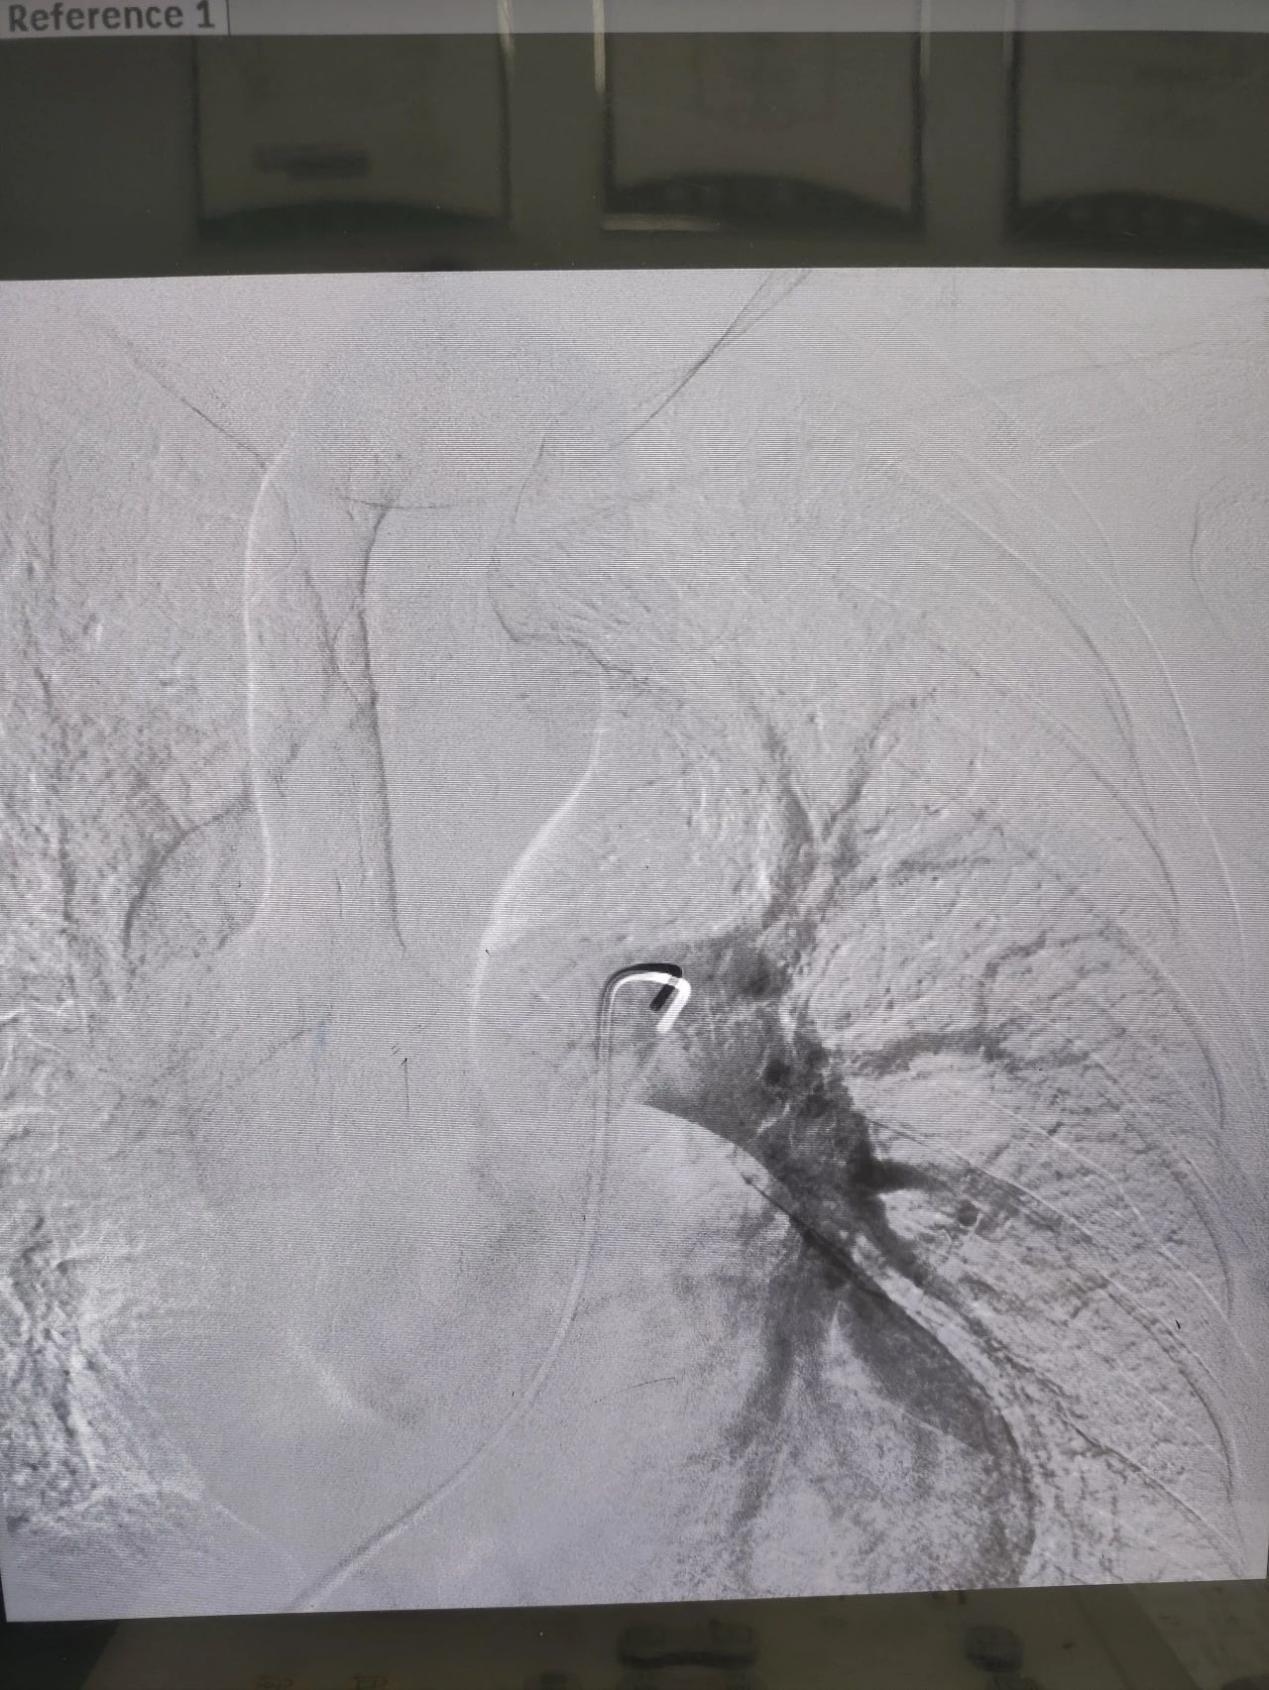

患者男性,69岁,2024年8月12日以“右侧下肢肿胀1周”在综合外科二病区就诊,后以“右下肢深静脉血栓形成”积极收住院治疗。次日查房时发现,患者血氧过低(约60%),我科援藏专家谢文涛主任考虑患者存在肺栓塞可能,立即主持科内术前讨论后建议立即行肺动脉造影介入治疗。经过40分钟的紧急手术治疗,左肺动脉主干血栓完全清除,为预防后期再次出现肺栓塞,同时下腔静脉置入可回收滤网。患者自身症状明显缓解,患者及家属对治疗效果非常满意,并于两周后,8月28日再次入住综合外科二病区,顺利取出可回收滤器。